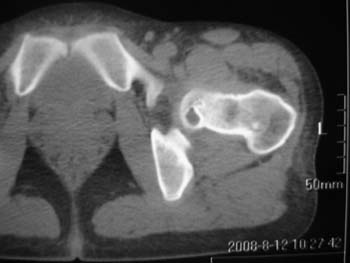

以下是引用358450m在2008-8-12 12:12:00的发言:[br]骨囊肿

以下是引用yangyudong333在2008-8-12 14:30:00的发言:[br]考虑退京变所致关节面下骨质囊变

以下是引用随光逐影在2008-8-12 20:40:00的发言:[br]考虑邻关节骨囊肿或骨内腱鞘囊肿。